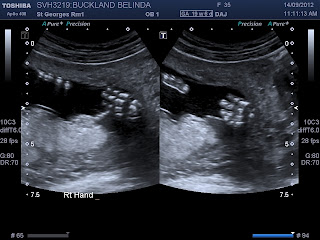

Brendon had booked today off and at 9 we headed into town. I had a 20 week scan booked and it was lovely to see our little baby.Baby moved around nicely - moving hands up and down, opening and closing mouth, swallowing and turning over. So that was really fun for the girls to see. The main reason for the scan was to check where the placenta was. I always feel more relaxed knowing it is not too low - and already it is well "out of the way".

Thankfully the placenta is posterior. My midwife had suspected it may be on the front again - like with Hezekiah. I know movements can be a lot less with that - so I was pleased it's at the back this time.We got some lovely photos of baby. Look how clearly we can see those leg bones.

And just look at those little hands. A lovely biology lesson for the girls too. Rachel immediately thought of her muscles and bones study that she did and I am sure her lapbook will come out when we get home.